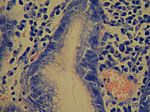

Helicobacter pylori-Gastritis, Giemsa